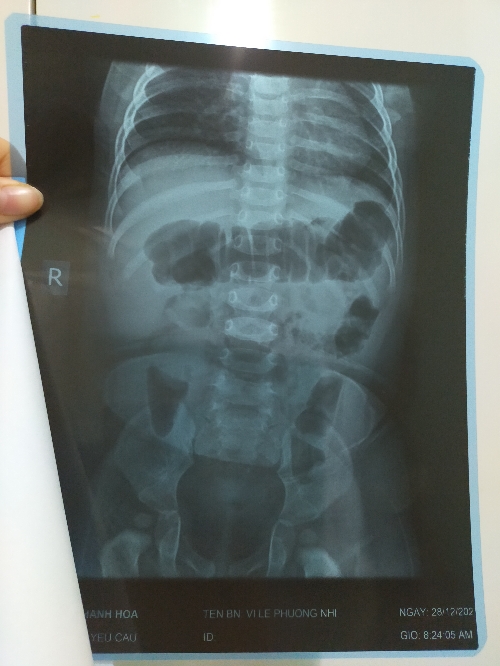

Chào bác sĩ, bé nhà e được 9 thang, e cho bé đi khám ở bệnh viện nhi thanh hoá biết bé có nang ở mạn sườn bên phải, mấy hôm vừa rồi bé có nôn, có lúc nôn cả ra dịch màu nâu thâm, bé bú ít, ăn ít. Mỗi lần nôn bé mệt lã người chỉ nằm ngủ ko chơi ko đùa. Mong các sĩ tư vấn giúp gia đình với ạ.

Với nang dịch kích thước 3cm cũng tương đối lớn. Tuy nhiên nang dịch này bản chất là dịch gì? Có phải u máu không? Có gây ra các triệu chứng tiêu hoá nôn; ăn kém ko thì bs cần hỏi em thêm một số triệu chứng nữa. Nếu có thời gian em đặt lịch khám bs để trao đổi trực tiếp nhé. Đặt lịch đơn giản lắm